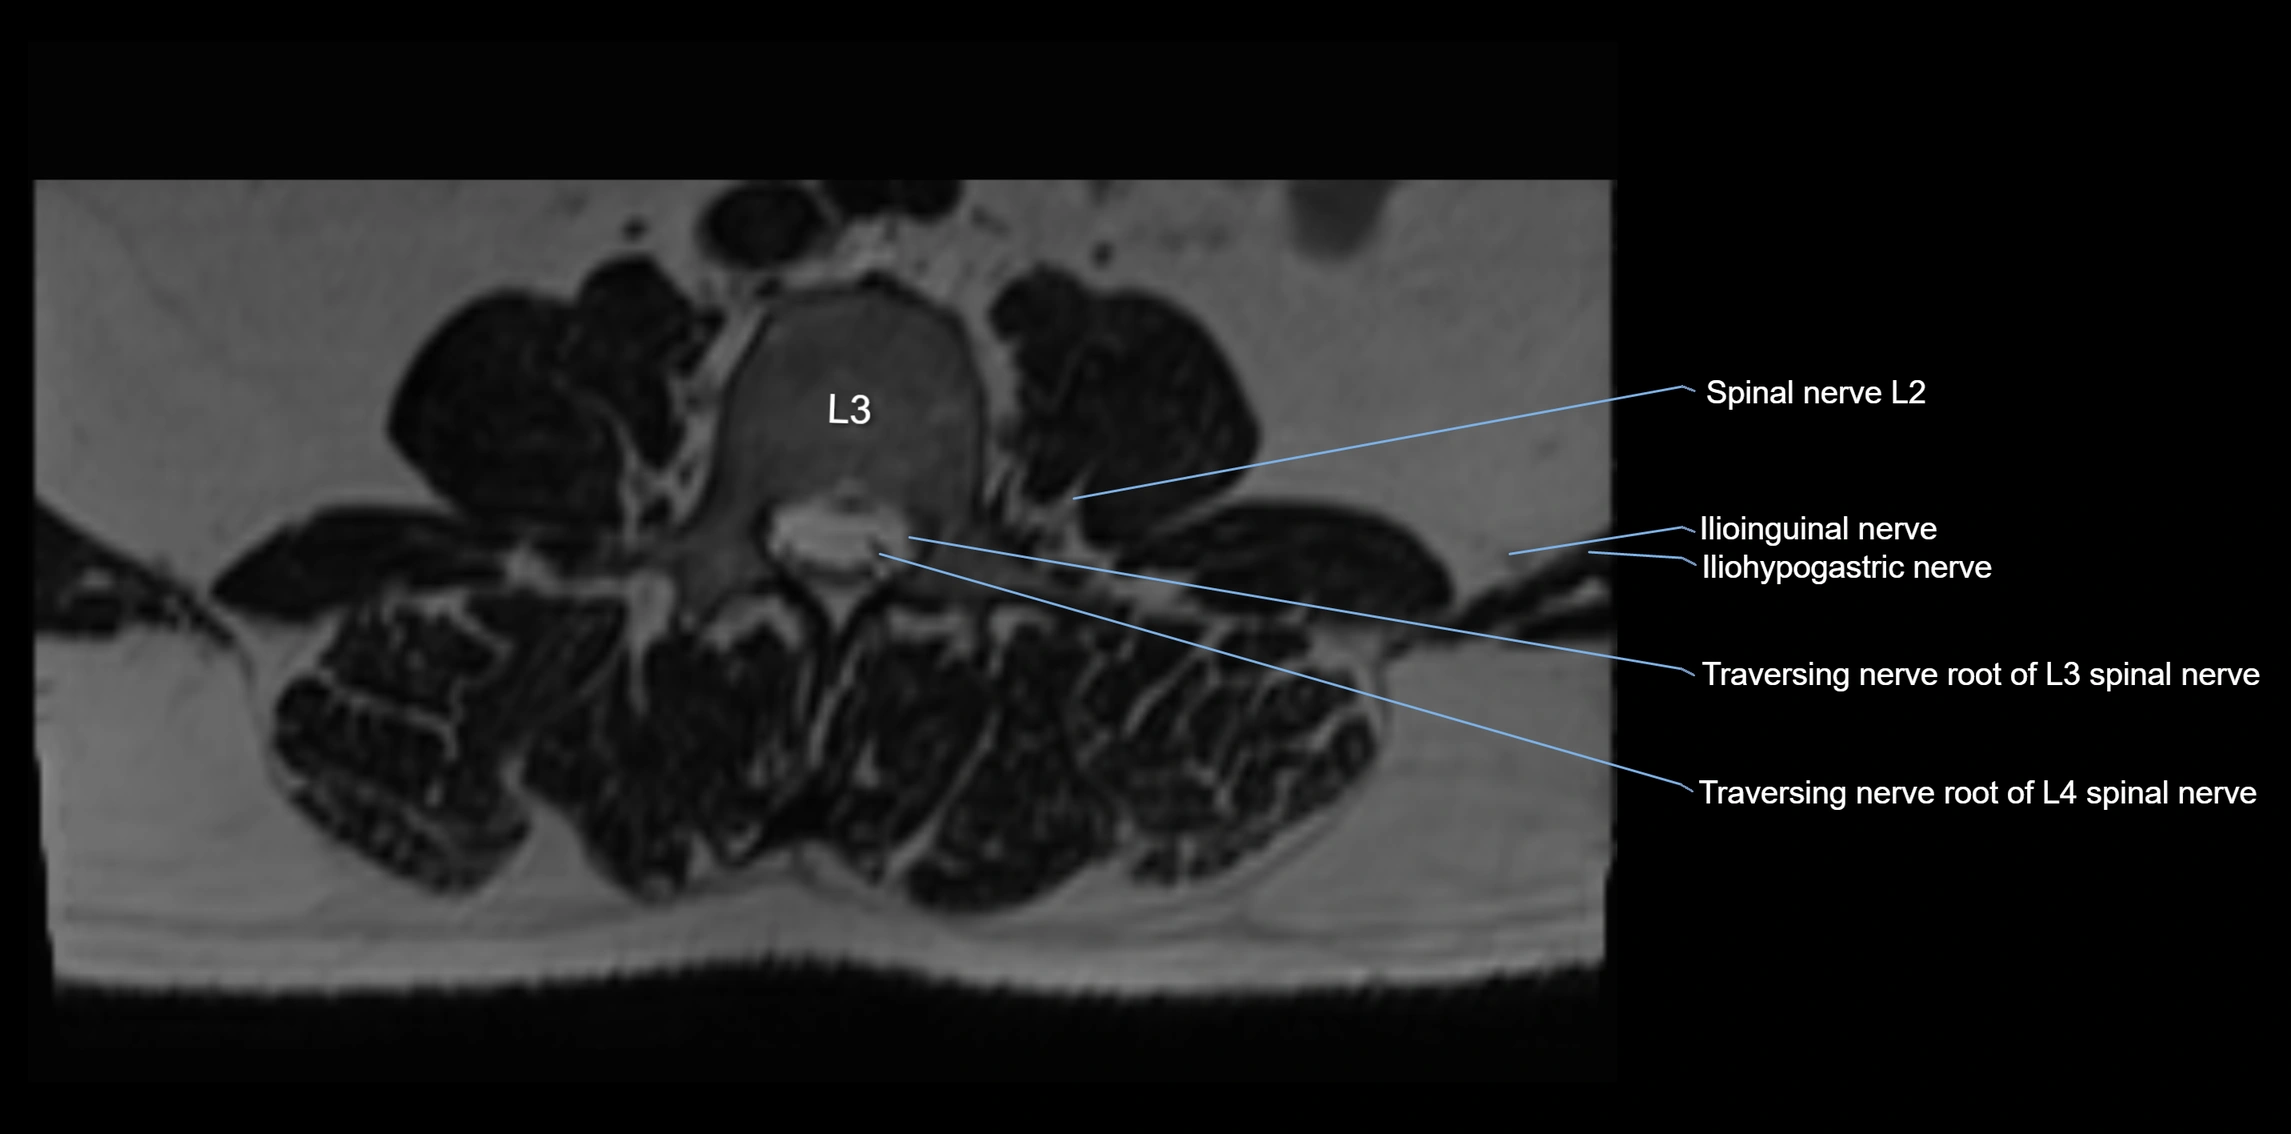

MRI image

image